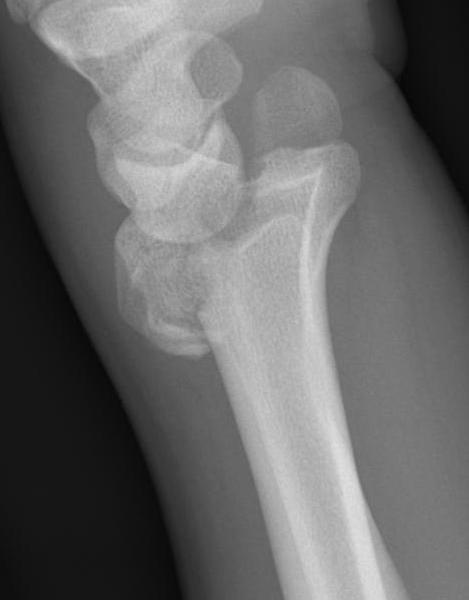

Dorsal ulna / volar ulna

Distal Radius Volar and Dorsal Ulna FragmentsDistal Radial Fracture CTDistal radius volar ulnar fracture

Distal Radius Dorsal Ulna FragmentDRUJ FractureDistal Radius Radioulna Fragments